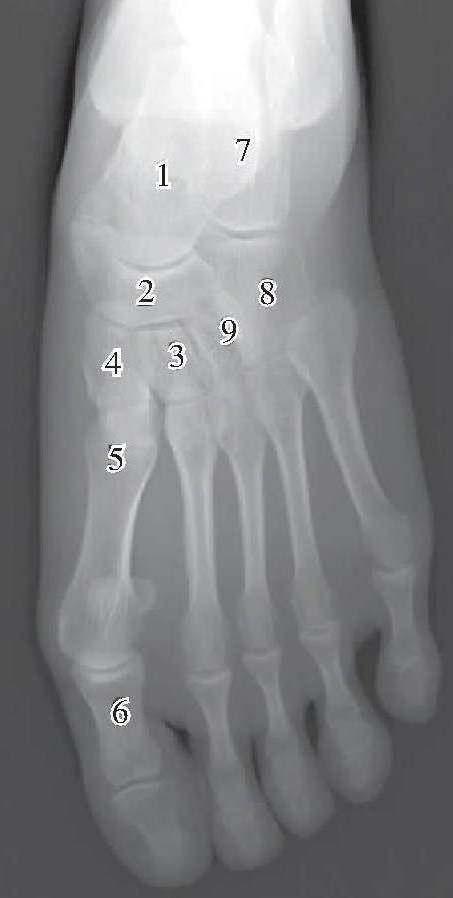

跗骨正位

1、距骨2、足舟骨3、中间楔骨4、内侧楔骨5、跖骨6、趾骨7、跟骨8、骰骨9、外侧楔骨

(1)距骨:大部与跟骨重叠不显影,只有距骨头可见轮廓,并与舟骨对应构成关节。

(2)跟骨:大部与距骨重叠不显影,只有其前端可见轮廓,并与骰骨对应构成关节。

(3)足舟骨:位居距骨头前方,呈横位四边形,其前方与3个楔骨对应构成关节,外侧与骰骨对应或部分重叠。内侧端突出游离,为舟骨粗隆。

(4)骰骨:呈方形,居跟骨与第4、5跖骨底之间,内侧缘与舟骨和第3楔骨都有重叠。

(5)内侧楔骨、中间楔骨、外侧楔骨:居足舟骨和第1、2、3跖骨底之间,其中内侧楔骨、中间楔骨影常较明显,而外侧楔骨与骰骨部分重叠难辨认。